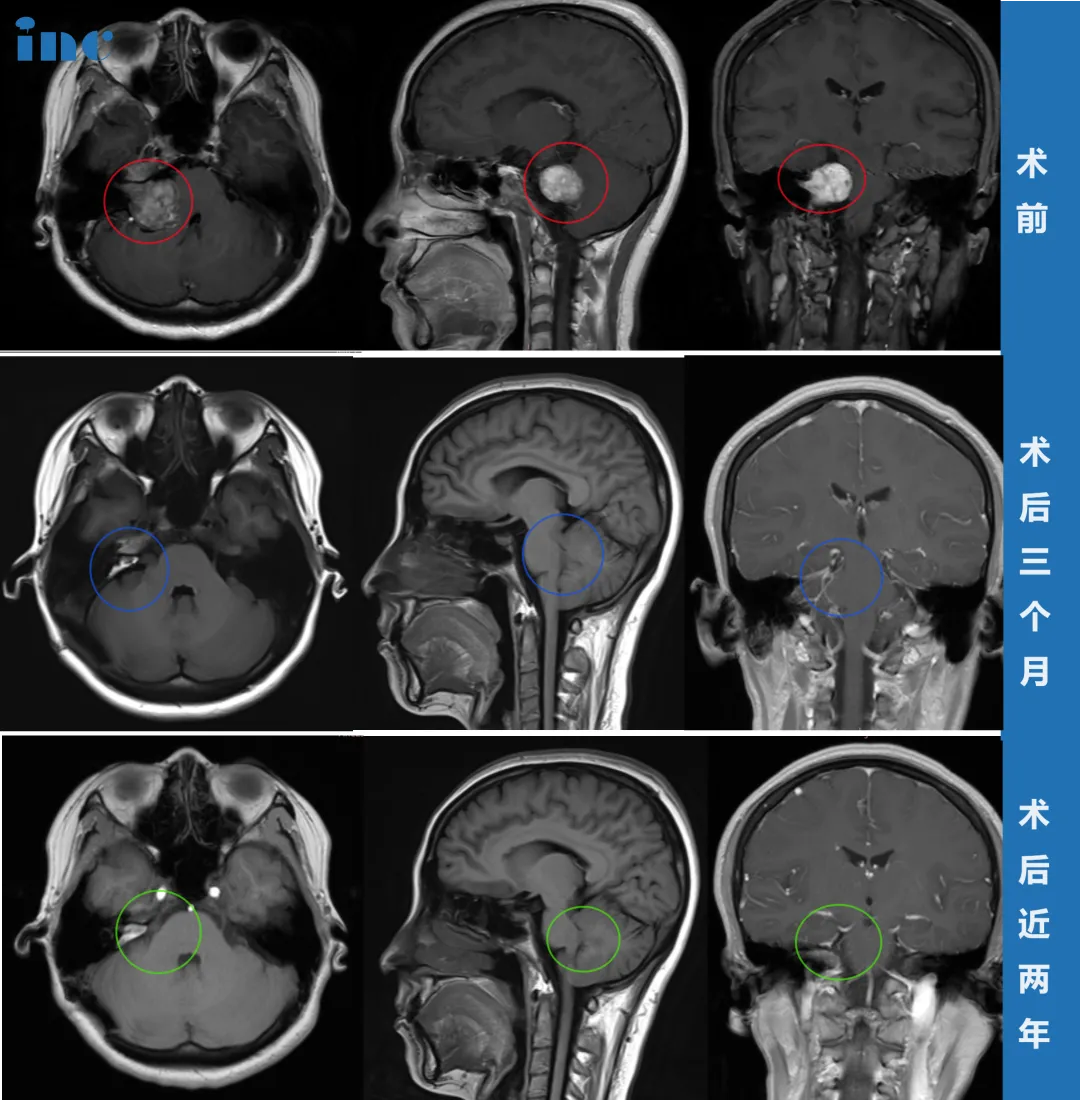

30余岁女性患者2019年始发耳部闷胀感,多次检查未见异常。2021年症状加剧,出现站立不稳、视力下降等表现,MRI确诊为3.5厘米听神经瘤压迫脑干。经过个体化手术入路结合神经电生理监测,实现肿瘤全切并保留面部功能。术后两年随访无复发迹象。